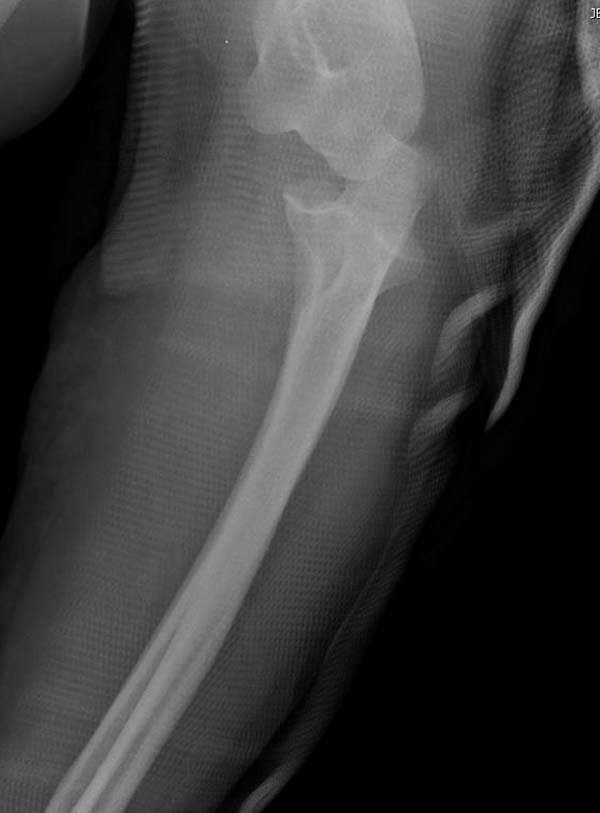

Для примера здесь случай начатый в другом центре, а потом переправленный к нам.

Снимки: 1-2 вывих, 4-5 вторичное смещение в гипсе, реконструкция латеральной связки и капсулы 13-14, повторный вывих после реконструкции, перевод в наш центр; 18-21 временная фиксация, 22-25 трансартикулярная фиксация и нестабильная головка фиксирована спицами, 29-30 амбулаторно, 32-33 после удаления винта и спиц...